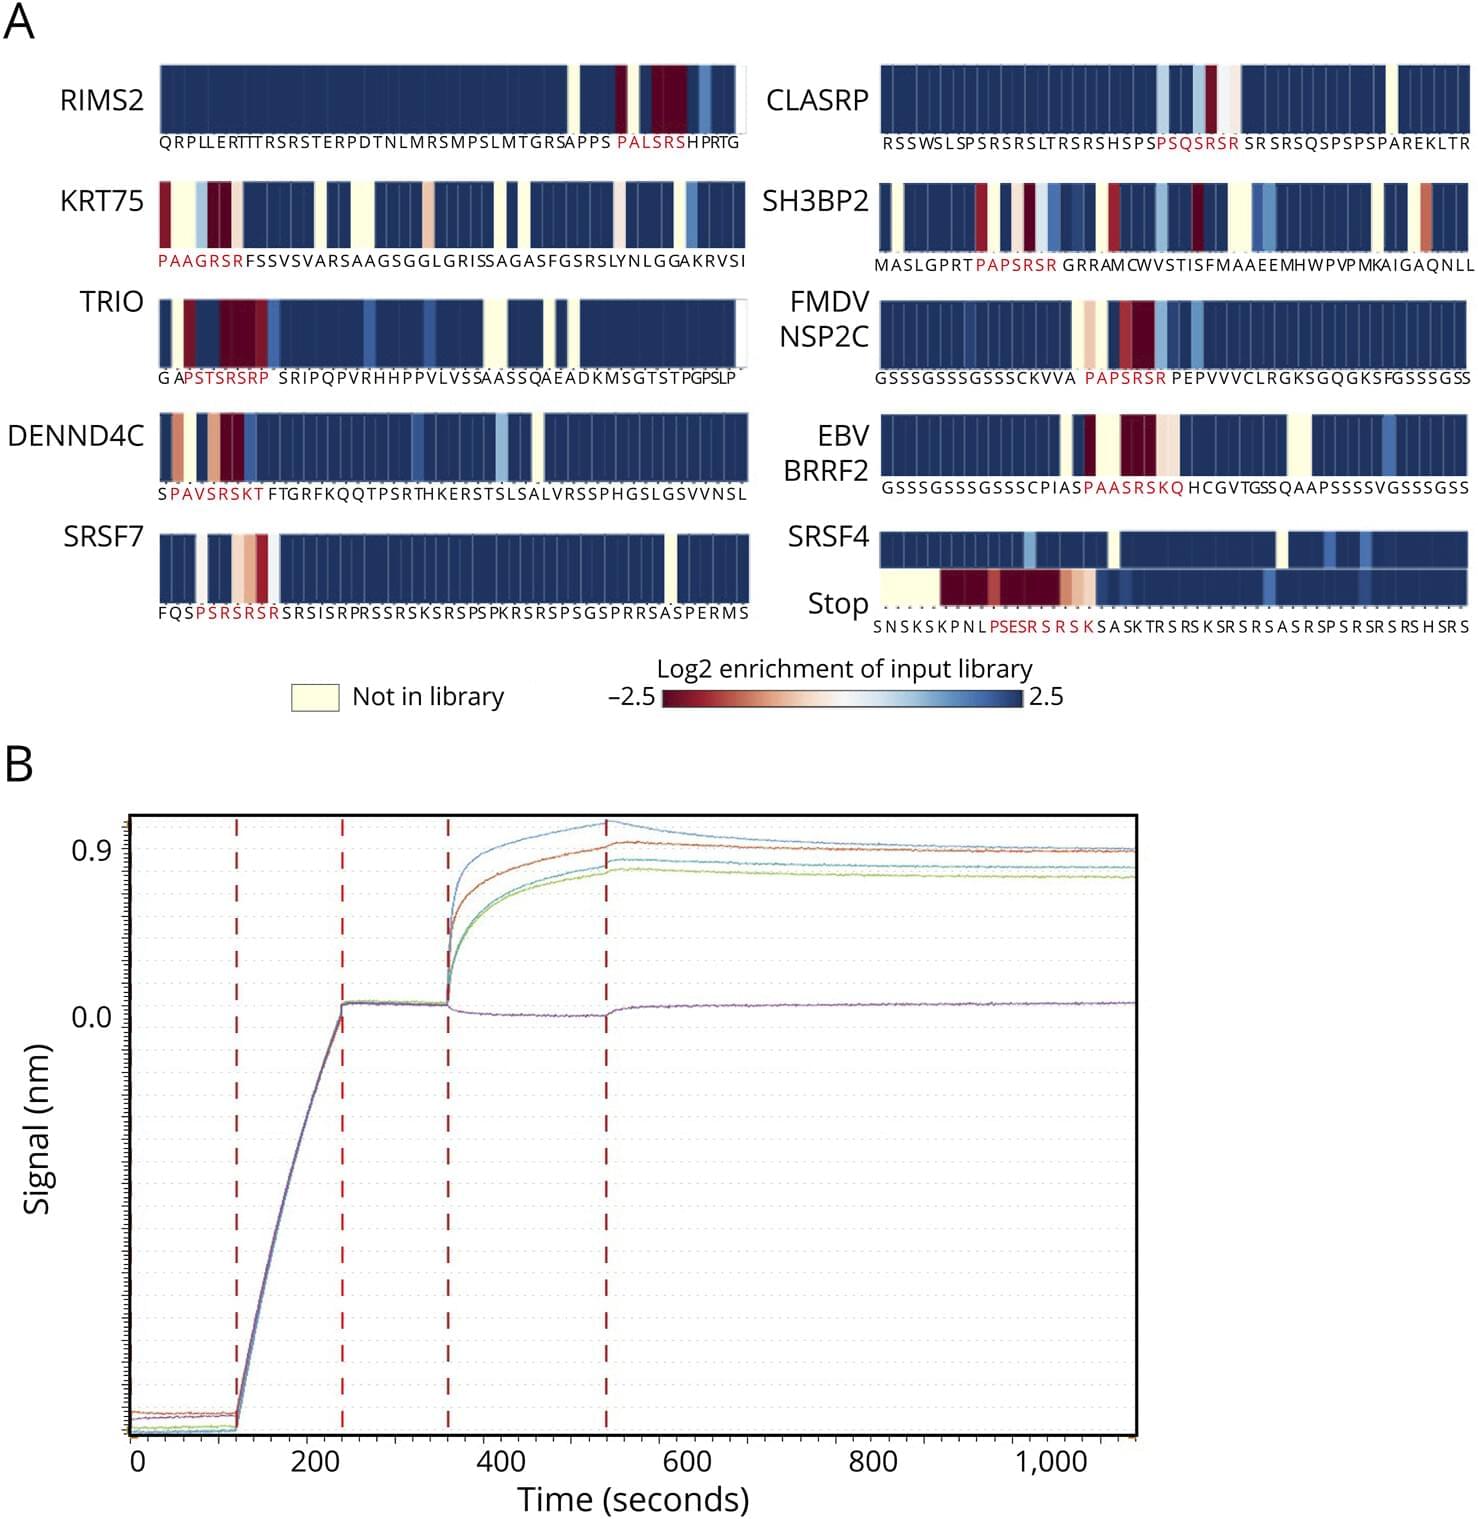

Background and ObjectivesMultiple sclerosis (MS) is a chronic progressive, demyelinating autoimmune CNS disease. Autoantibodies to the motif P-(SA)-x-(SGA)-R-(SN)-(LRKH) are a class of predictive markers specific to MS that could add to emerging…